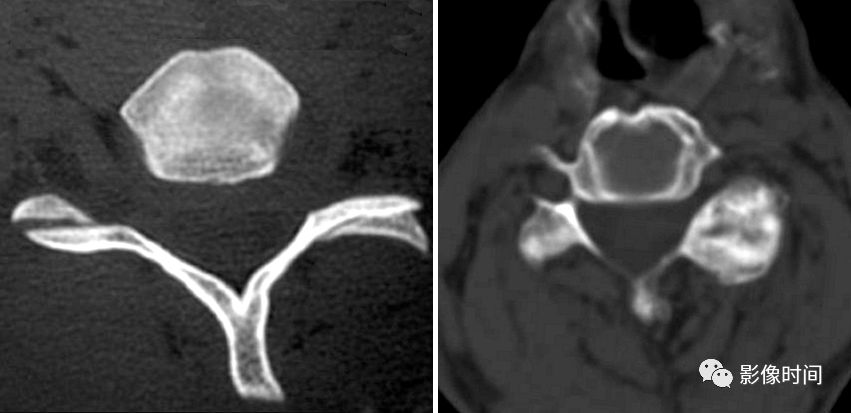

2裸面征

裸面征(naked facet sign),又称反汉堡面包征(reverse hamburger bun sign)

当脊椎小关节脱位时,上关节突脱位可位于上关节突后方,关节面向下显露,表现为关节面裸露,为裸面征(黄箭)。脱位可单侧或双侧出现;本例为左侧脱位,右侧为半脱位:可见上关节突(红箭)外移,相对下关节面显露,表现为关节面部分裸露(白箭之间)。

这是屈曲分离型损伤的特点,提示有严重的韧带损伤和脊柱不稳。

典型病例

正常汉堡包征的小关节(下图);外伤后,CT 骨窗示其前部「面包」(上关节突,黑箭)后移,位于下部「面包」(下关节突,白箭)的后方,关节面裸露。